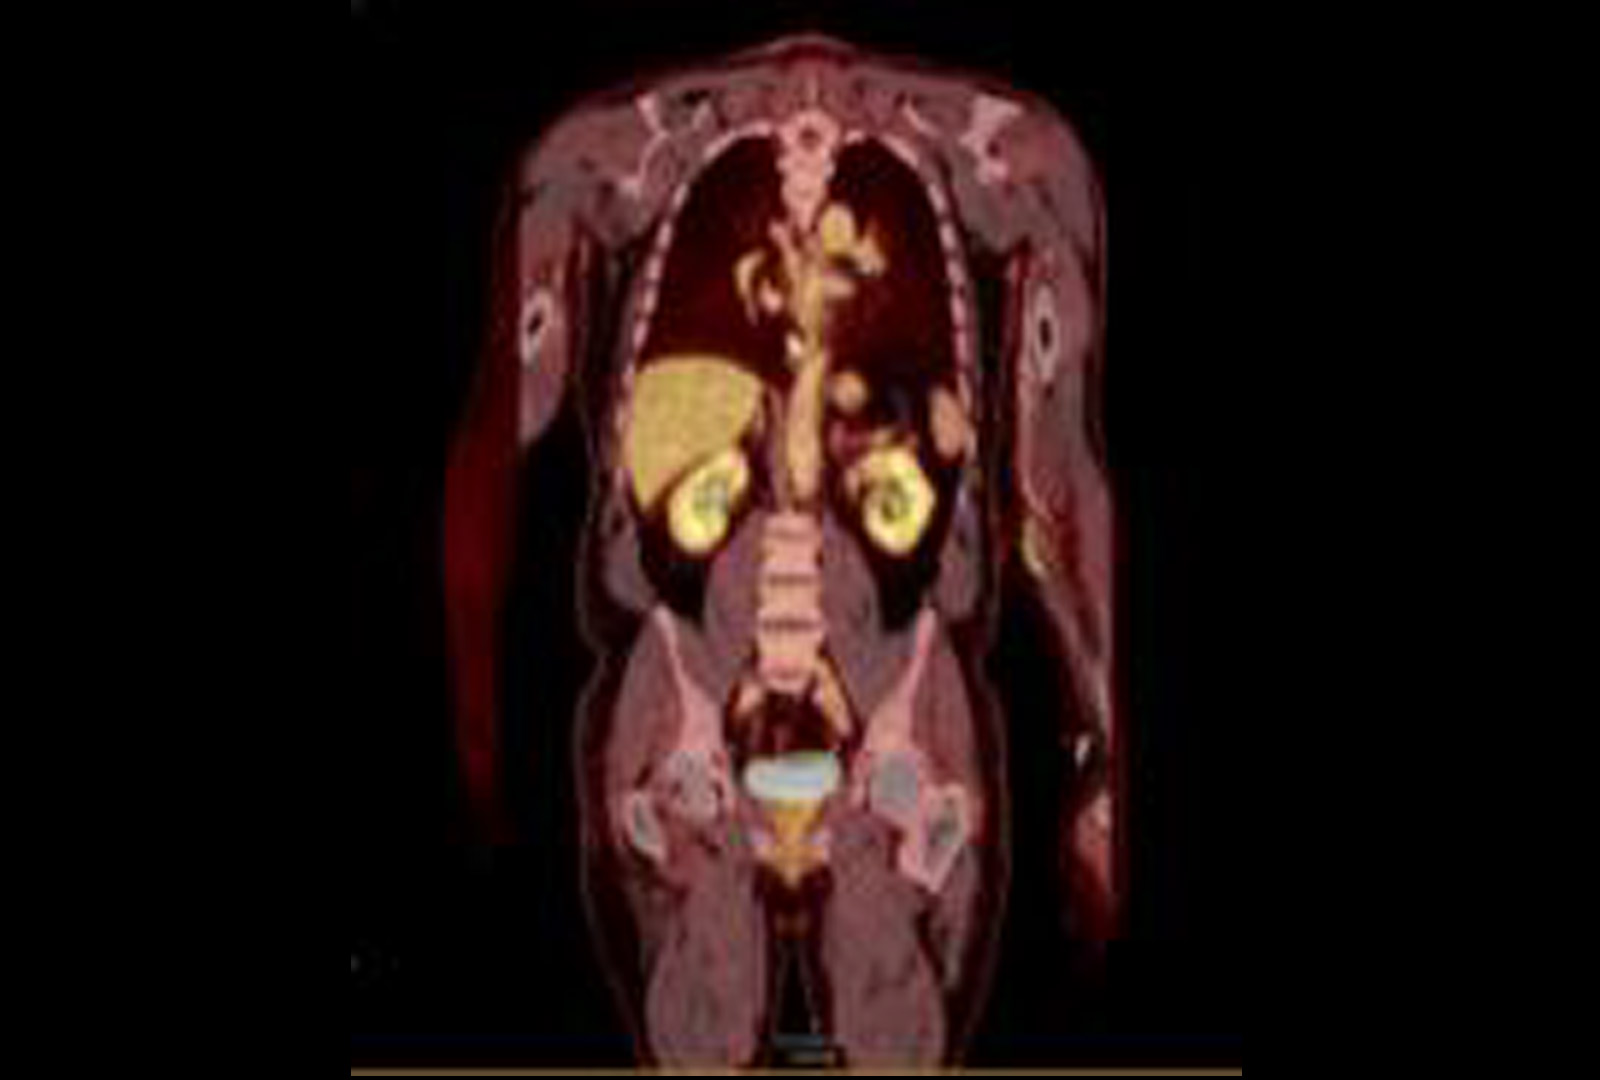

Further FDG Uptake in the Prostate

PET/CT demonstrating FDG uptake in the left basal to mid prostate correlating with elevated PSA. Source: NYU Langone Health